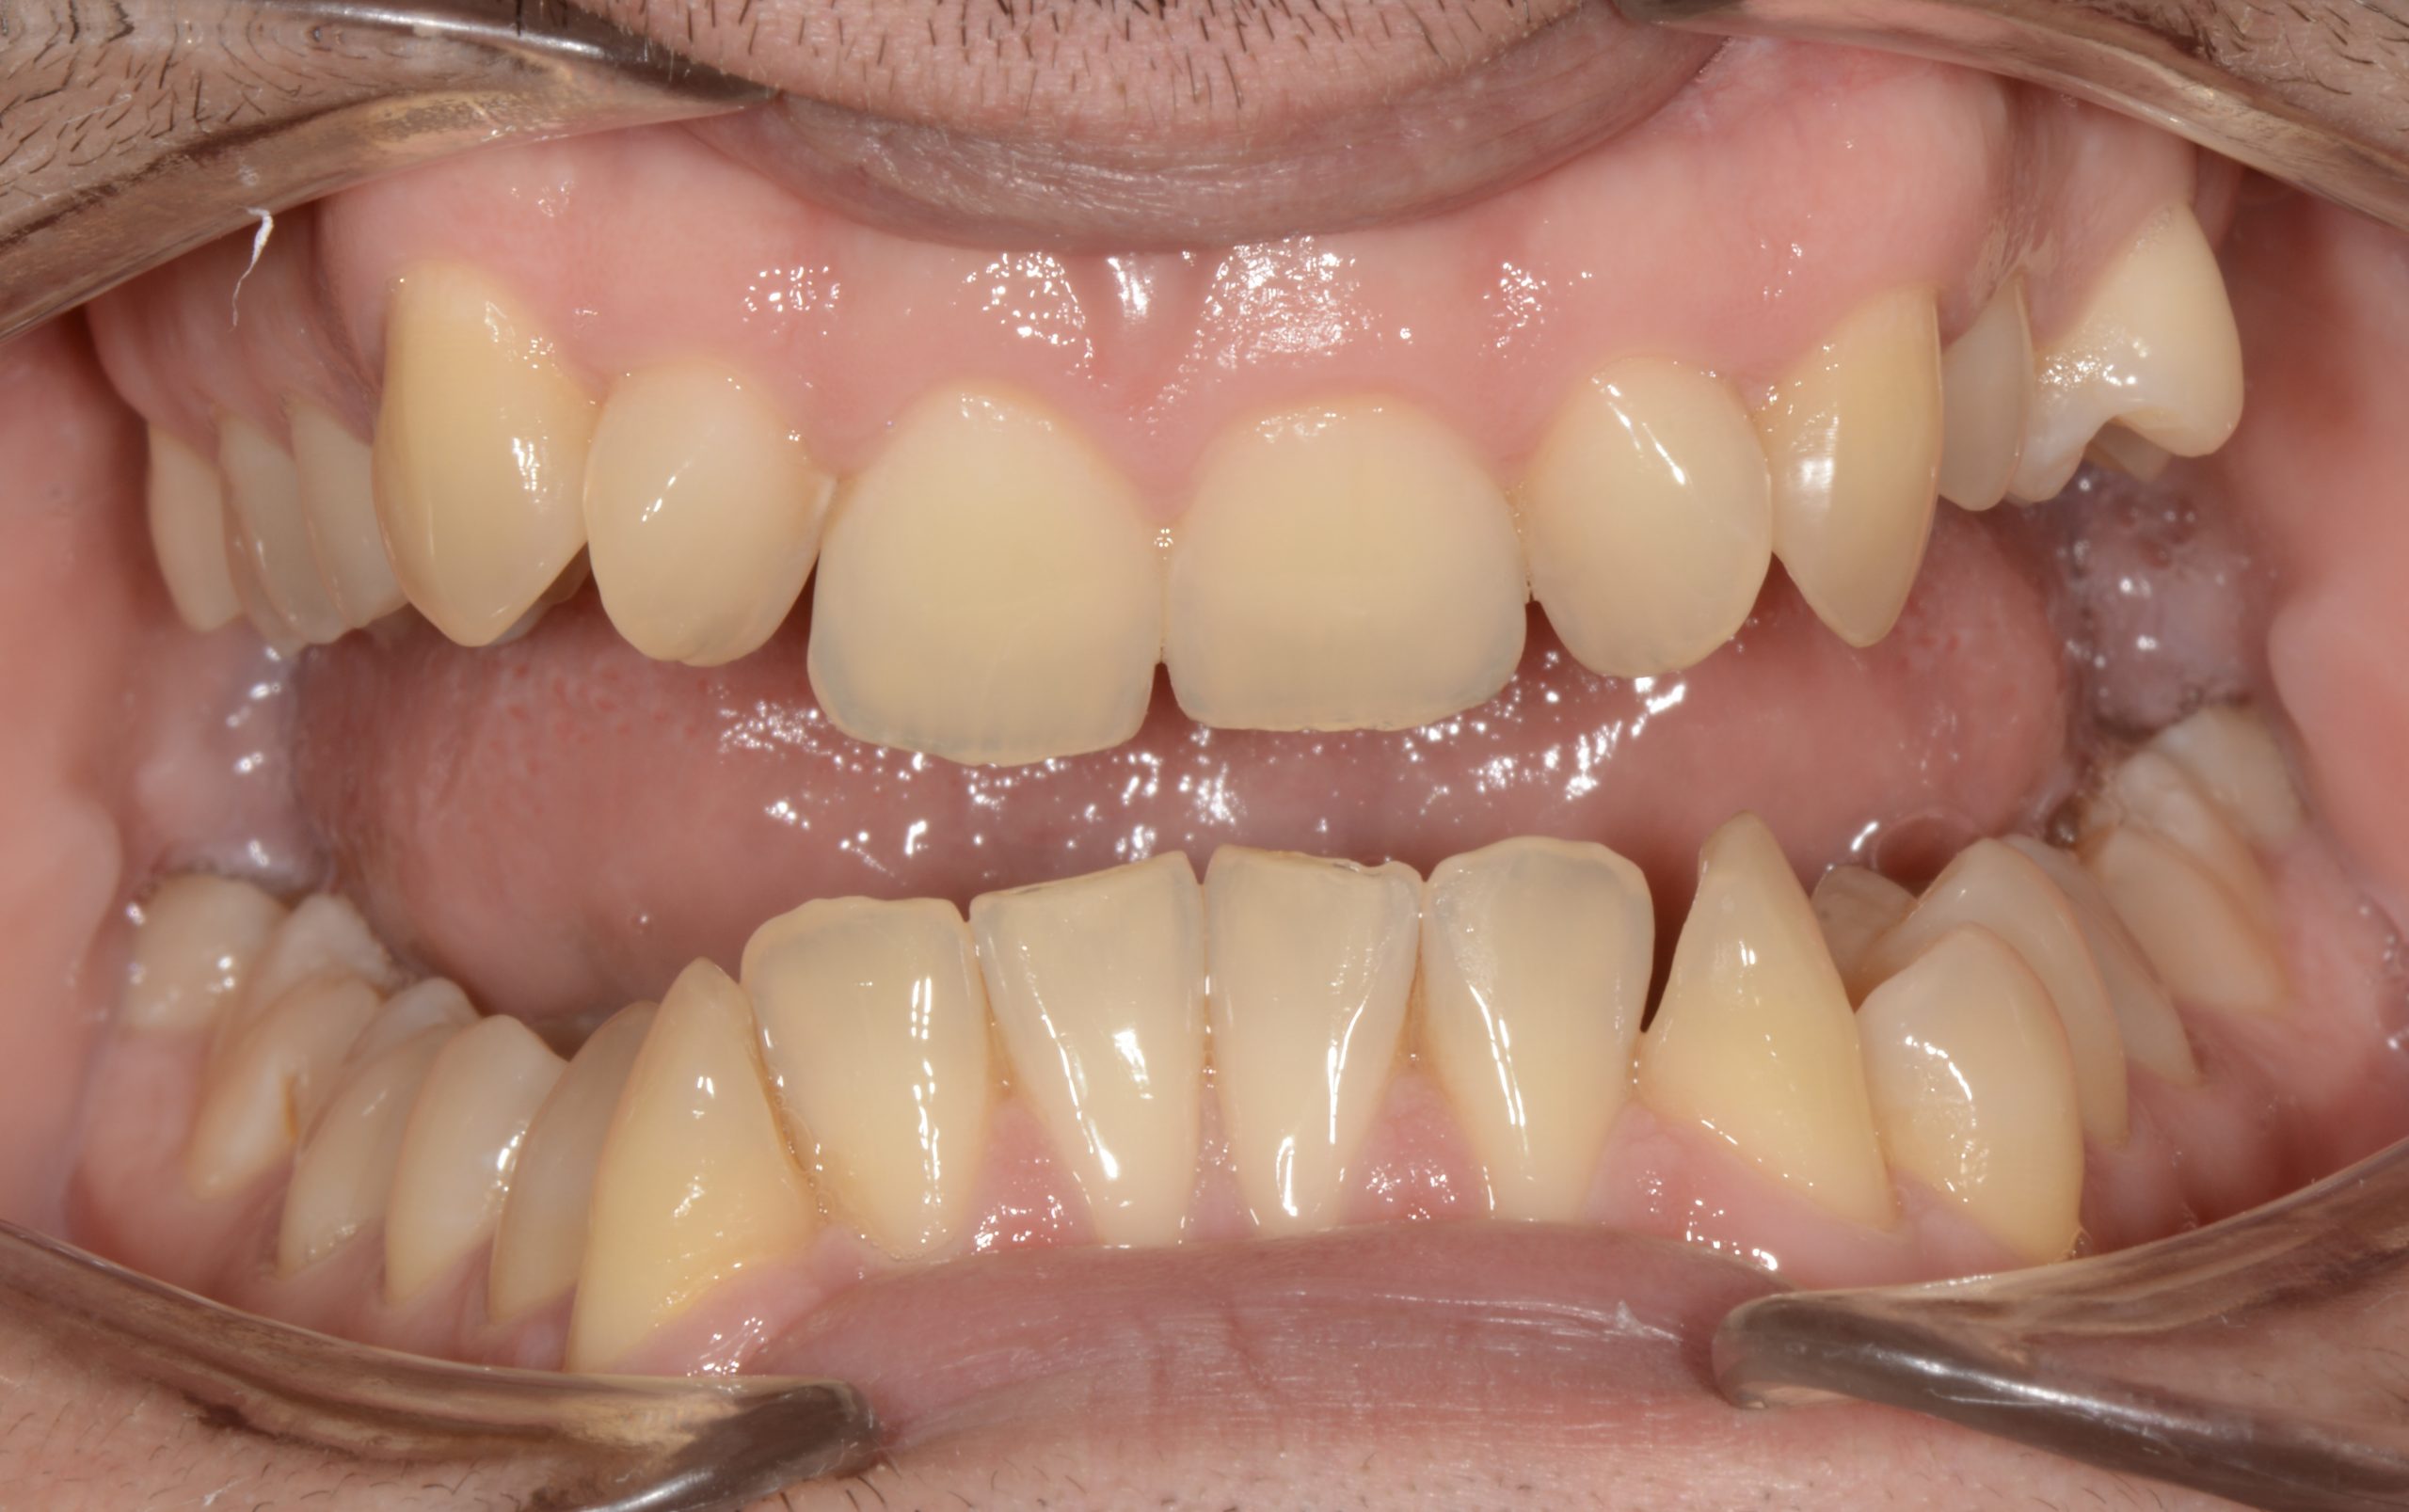

Az elmúlt évekből rengeteg szakmai referenciát tudnánk bemutatni, amelyek különböző fogszabályozási problémákat oldottak meg. Válogatva a több száz esetből, ezen az oldalon olyan képeket, információkat igyekeztünk bemutatni, amelyeknek a segítségével a jövőbeni pácienseinknek azt tudjuk üzenni: A Te fogsorod is lehet gyönyörű!

(Képeket a Pácienseink külön írásos beleegyezésével mutatjuk be!)